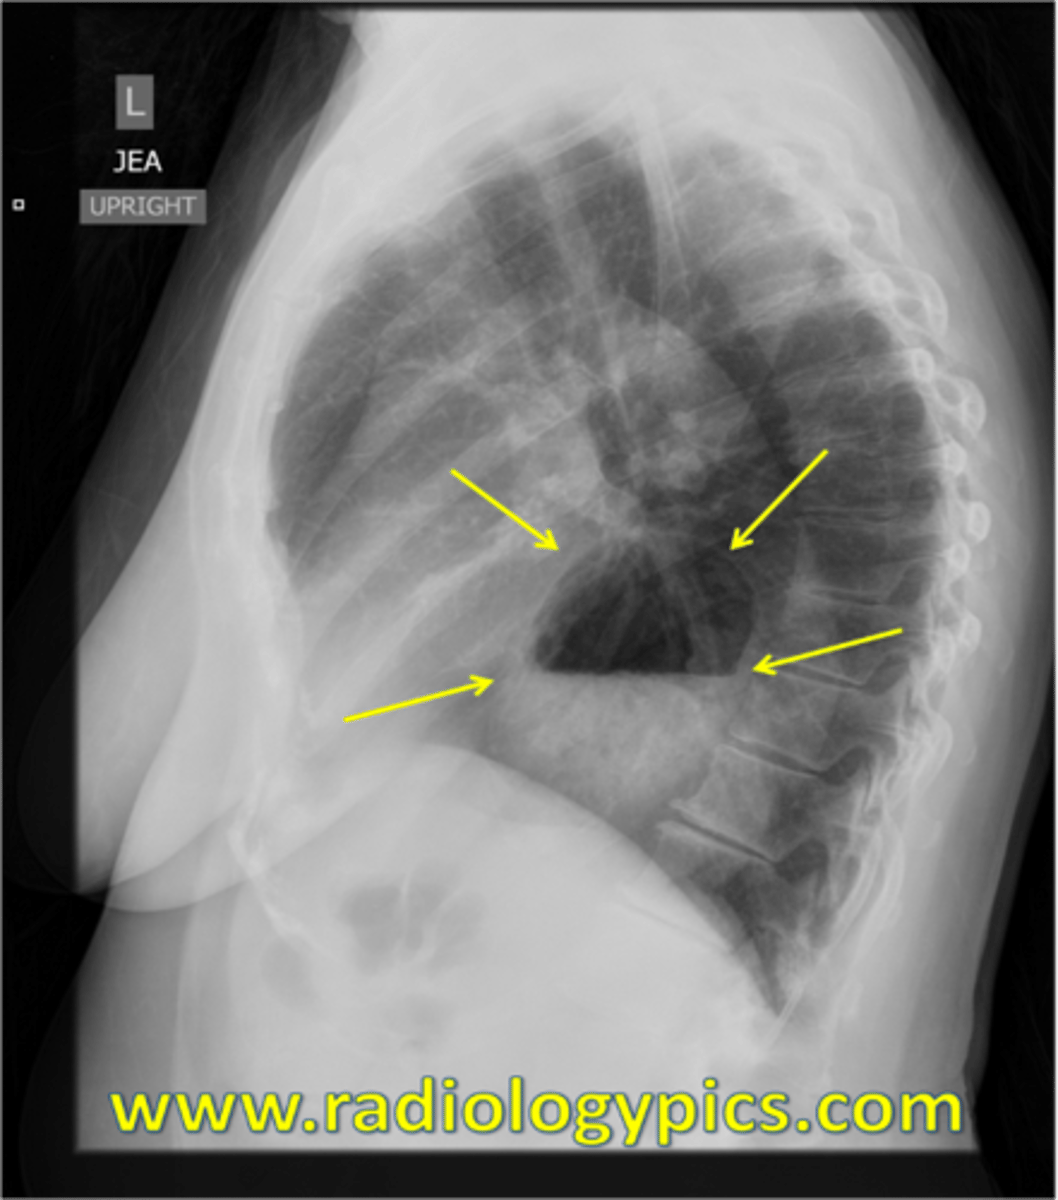

Hiatal hernia CXR

Hiatal hernia CXR (Pic 2)